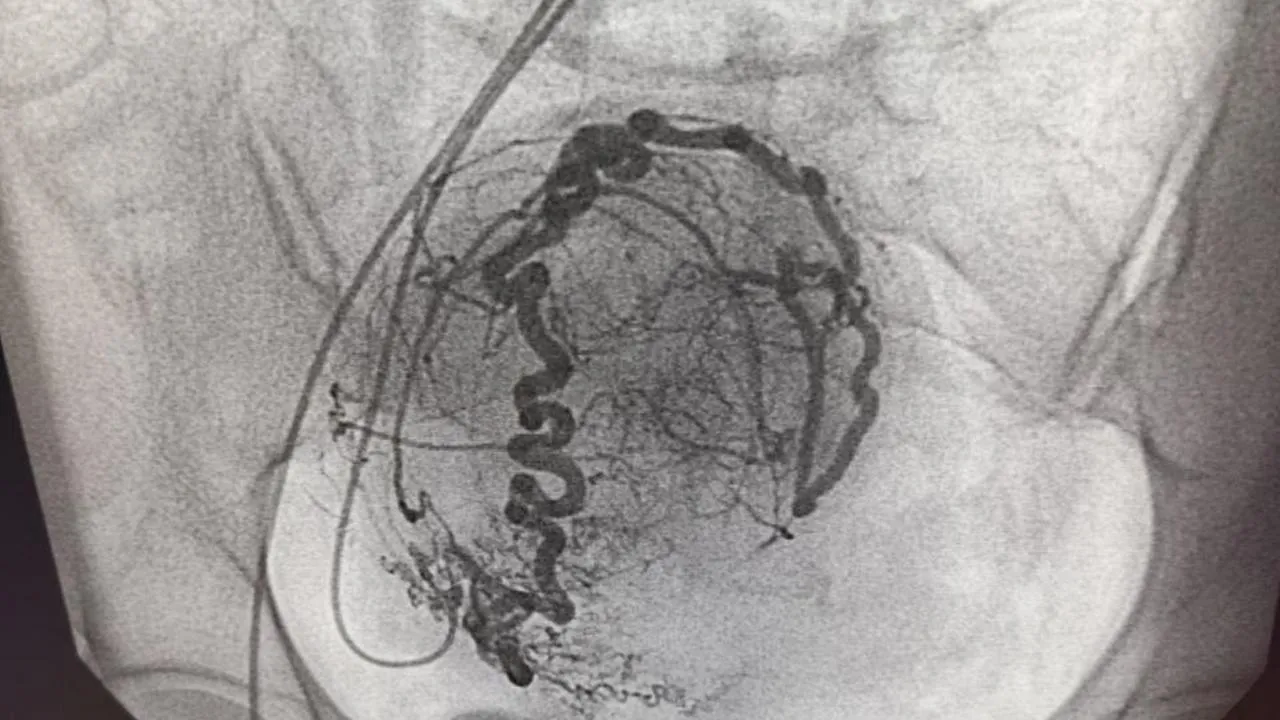

Операция длится от 20 минут до полутора часов. Ее проводит эндоваскулярный хирург в рентгеноперационной с применением специального оборудования.

Во время процедуры хирург делает небольшой прокол в бедре и вводит катетер в сосуды, которые питают опухоль. Затем в сосуды вводятся специальные микросферы — эмболы. Они блокируют кровоток, и миоматозные узлы постепенно разрушаются.

После эмболизации опухоль начинает уменьшаться в размерах. Женщины отмечают, что боль исчезает, а менструации становятся нормальными. Восстановление после операции может занять до шести месяцев. Все это время пациентку сопровождает врач-гинеколог.